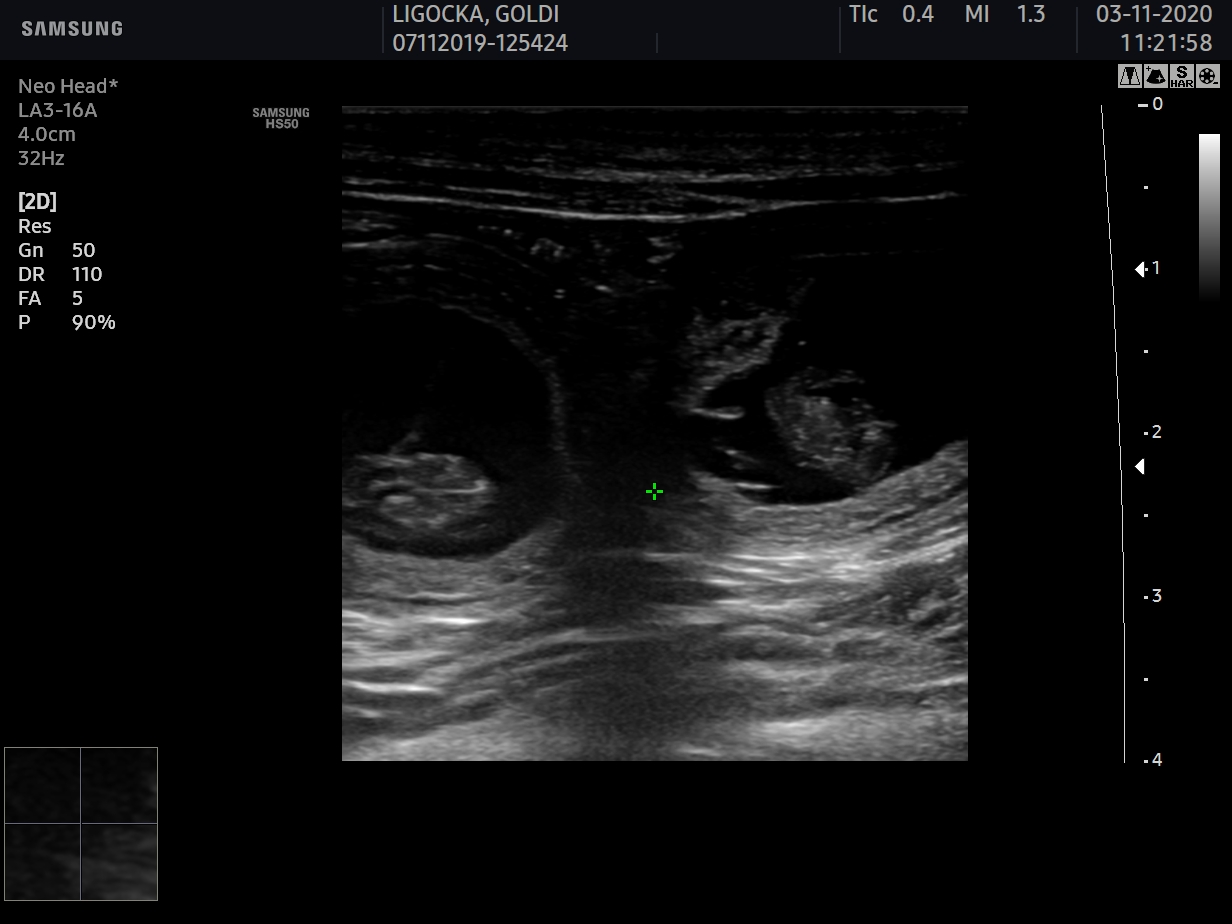

usg